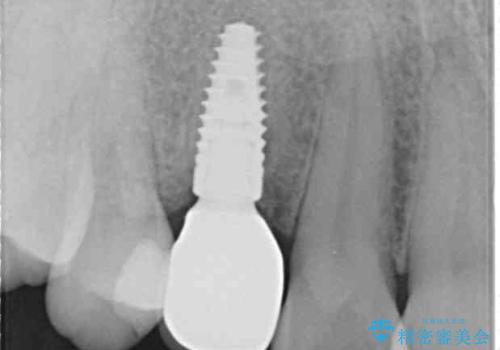

2本の歯が前後に重なった状態でむし歯となっていたので、抜歯後に歯肉や骨の状態が落ち着くのを待ち、インプラントを埋入することとしました。

崩壊した歯は全て抜去し、他人から見える位置の歯はセラミッククラウンが装着され、整った口腔環境となりました。